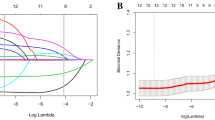

We collected data of 900 consecutive patients (634 males) with bilateral (428) or unilateral non-traumatic osteonecrosis diagnosed before collapse (at stage I or stage II). The follow-up was average five years (3 to 8 years). A total of 50 variables related to the osteonecrosis were included in the study. The osteonecroses were randomly divided into a training set (80%) and a validation set (20%) with a similar percentage of hips with collapse in the two groups. Machine learning (ML) algorithms were trained with the selected variables. Performance was evaluated and the different factors (variables) for collapse were ranked with Shapley values. The primary outcome was prediction of occurrence of collapse from automated inventory systems.

In this series of patients, the accuracy with machine learning for predicting collapse within three years follow-up was 81.2%. Accuracies for predicting collapse within six to 12-24 months were 54.2%, 67.3%, and 71.2%, respectively, demonstrating that the accuracy is lower for a prevision in the short term than for the mid-term. Despite none of the risk-factors alone achieving statistical significance for prediction, the system allowed ranking the different variables for risk of collapse. The highest risk factors for collapse were sickle cell disease, liver, and cardiac transplantation treated with corticosteroids, osteonecrosis volume > 50% of the femoral head. Cancer (such as leukemia), alcohol abuse, lupus erythematosus, Crohn’s disease, pemphigus vulgaris treated with corticosteroids, and osteonecrosis volume between 40 and 50% were medium risk factors for collapse. Familial cluster of collapse, HIV infection, chronic renal failure, nephrotic syndrome, and renal transplantation, when treated with corticosteroids, stage II, osteonecrosis volume between 30 and 40%, chemotherapy, hip pain with VAS > 6, and collapse progression on the contralateral side, were also significant but lowest risk factors. A heat map is proposed to illustrate the ranking of the combinations of the different variables. The highest risk of collapse is obtained with association of various risks factors.

Lundberg SM, Lee S-I. A (2017) unified approach to interpreting model predictions. NIPS; New York: Curran Associates; 4765–4774

Meng Y, Yang N, Qian Z, Zhang G (2020) What makes an online review more helpful: an interpretation framework using XGBoost and SHAP values. J Theor Appl Electron Res 16(3):466–490. https://doi.org/10.3390/jtaer16030029]